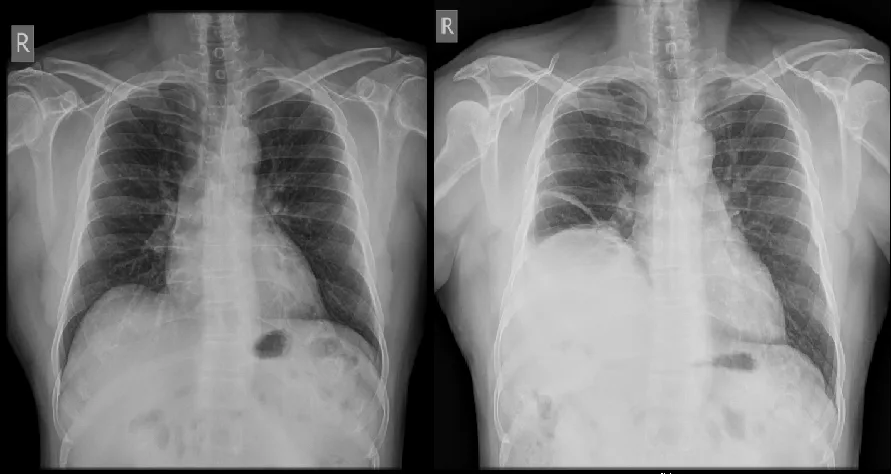

ENT Quiz – I feel breathless!

A 42-year-old male patient presented with a non-healing ulcer on the right lateral border of the tongue for 3 months. A biopsy from the lesion proven to be well-differentiated squamous […]